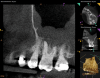

As part of the endodontic evaluation, CBCT imaging showed periapical pathology associated with tooth No. 14 as well as significant MSEO (Figure 7 and Figure 8). Clinical testing confirmed the absence of a cold response but no tenderness to percussion or palpation. A composite buildup was in place, absent evidence of recurrent decay. Soft tissues were unremarkable.

Fig 7 and Fig 8. Preoperative CBCT scans showing evidence of periapical pathology on tooth No. 14 as well as communication with the adjacent maxillary sinus and associated mucositis. Fig 7: Sagittal view, buccal roots No. 14. Fig 8: Sagittal view, palatal root No. 14.

Figure 7

Fig 8. Preoperative CBCT scans showing evidence of periapical pathology on tooth No. 14 as well as communication with the adjacent maxillary sinus and associated mucositis. Fig 7: Sagittal view, buccal roots No. 14. Fig 8: Sagittal view, palatal root No. 14.

Figure 8